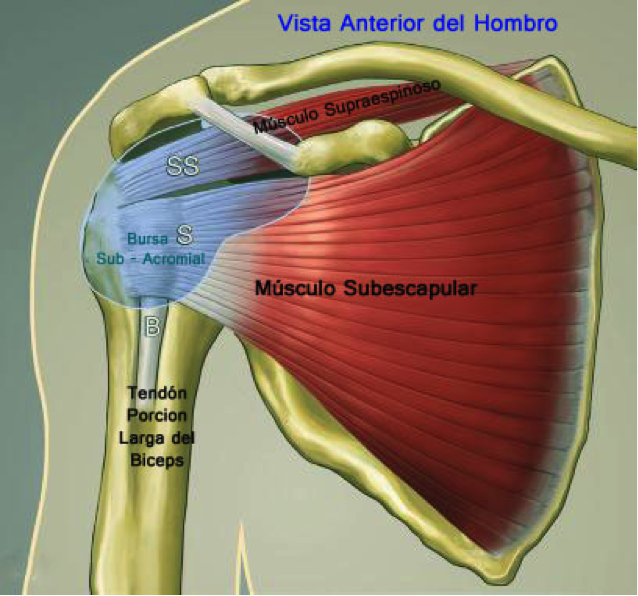

Фотографии мышц ротаторной манжеты плеча